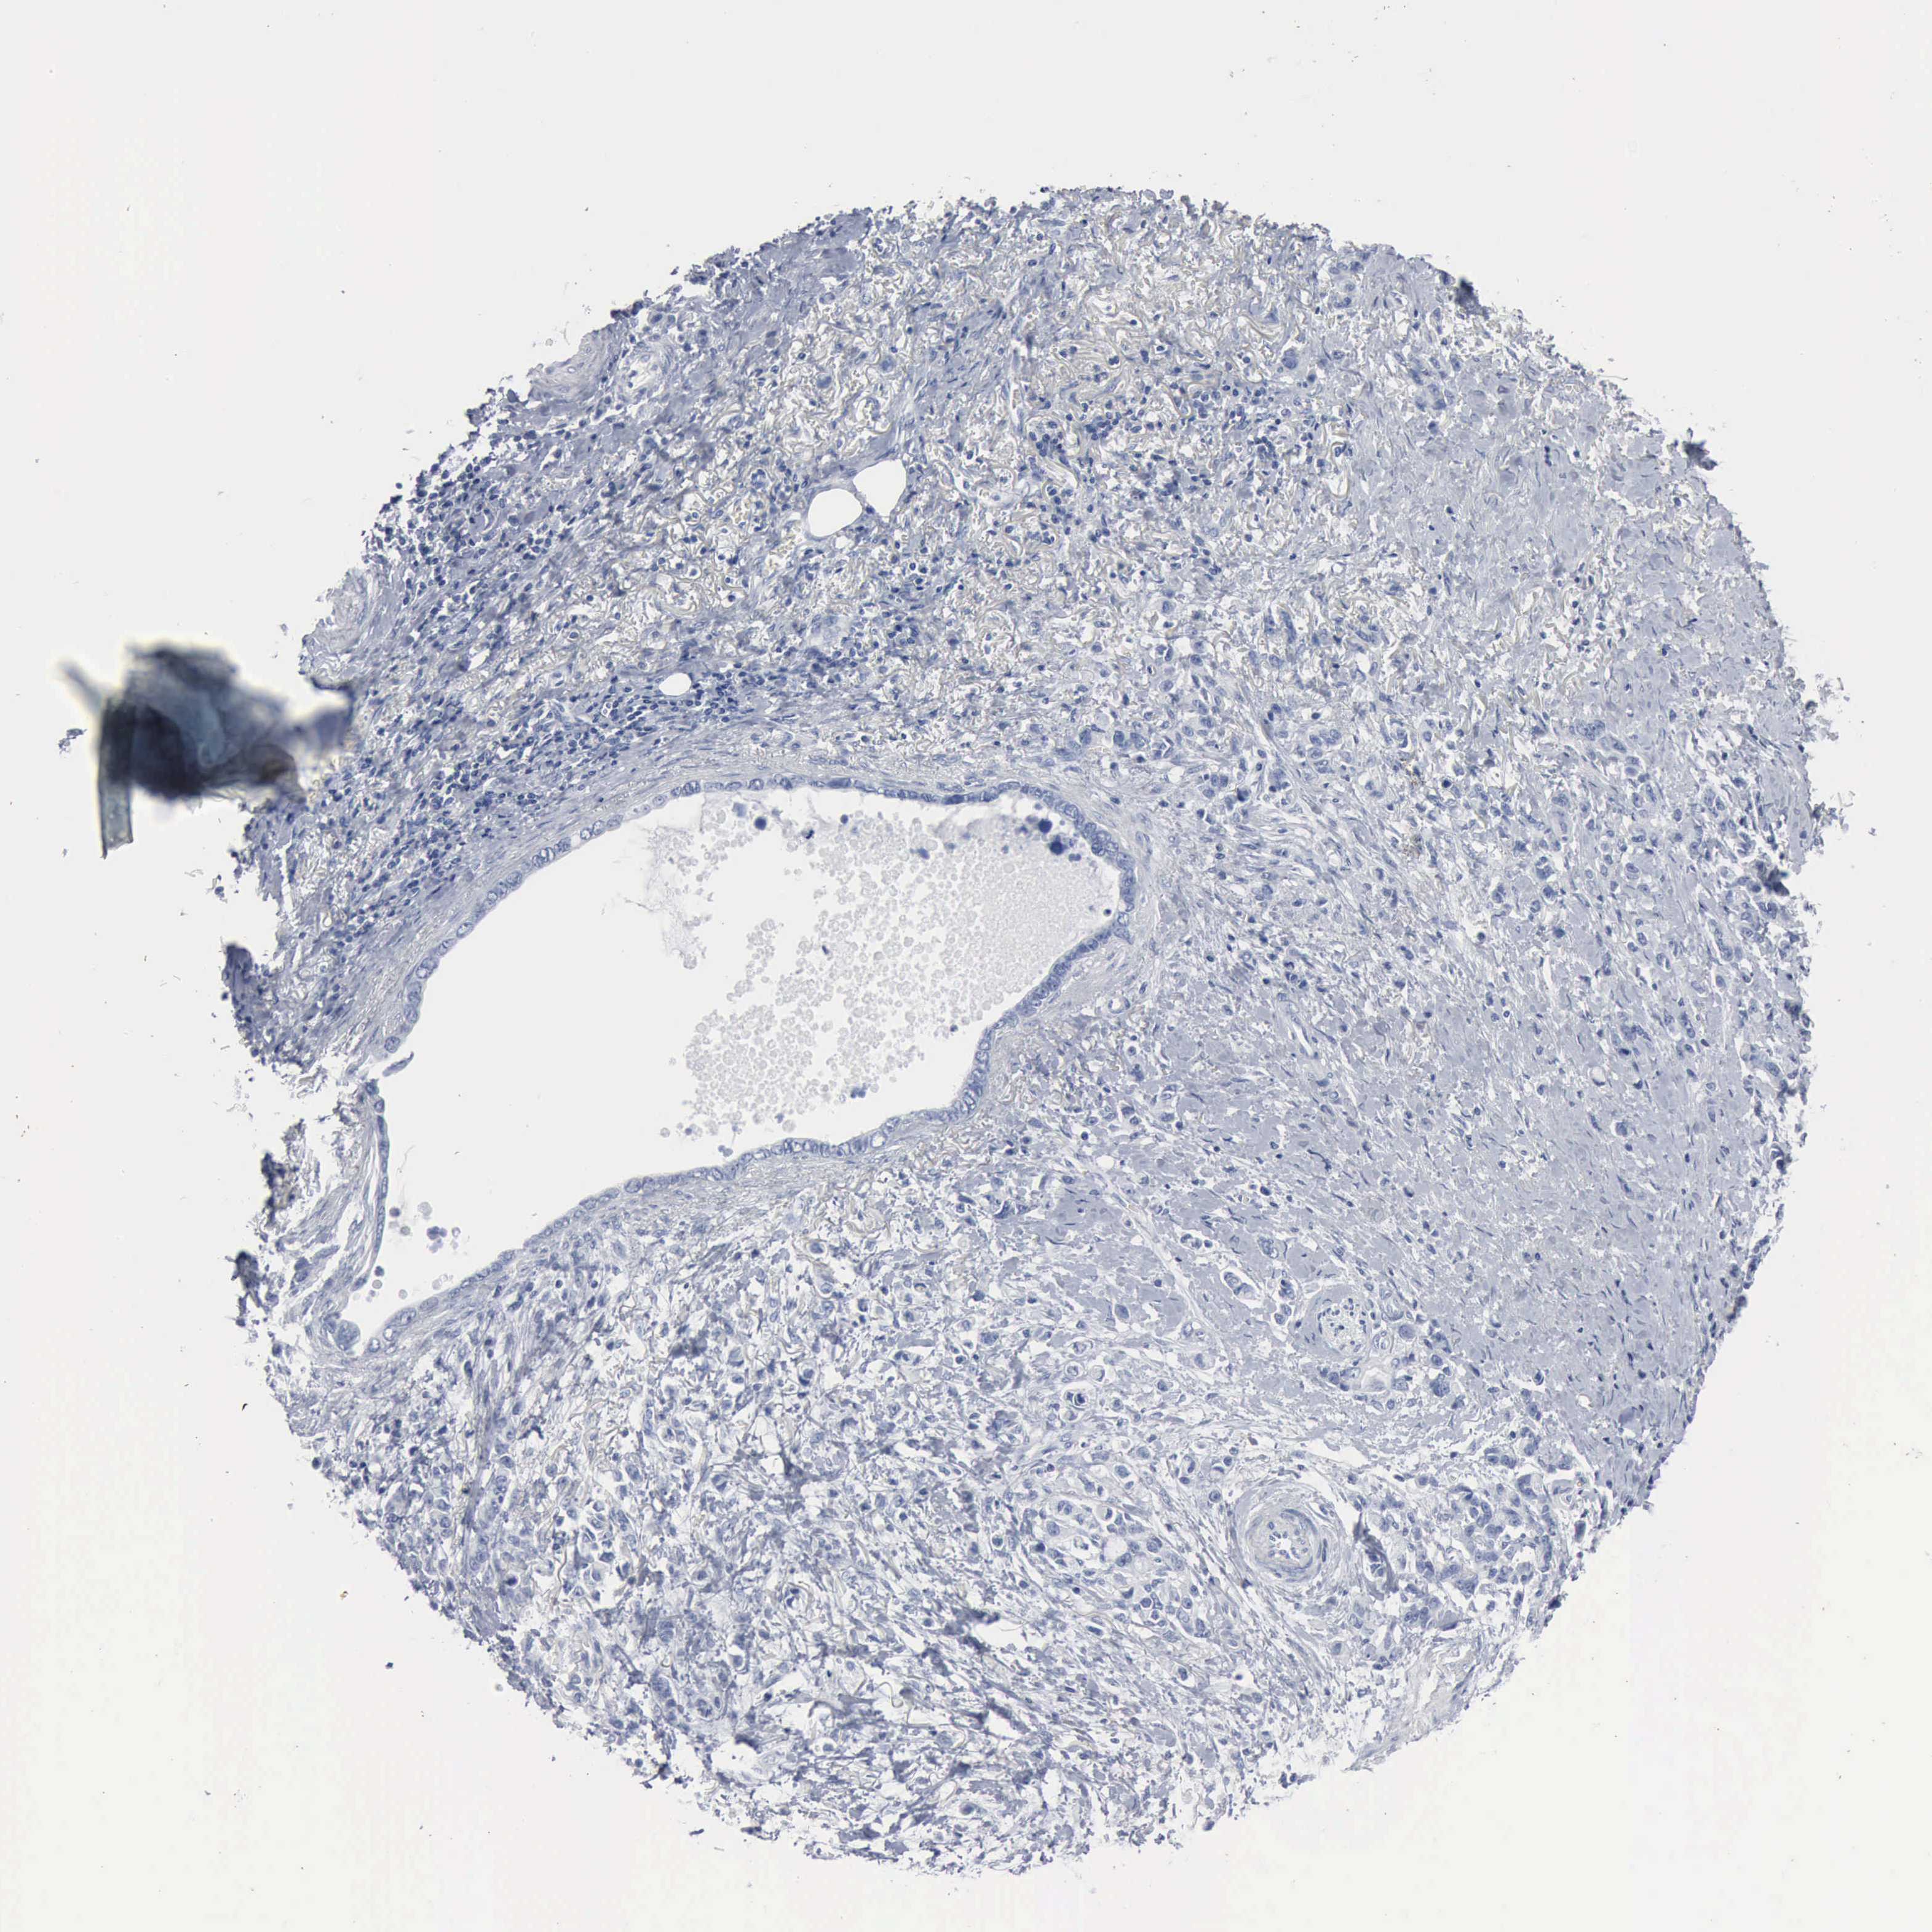

STOMACH CANCER - Protein expressioni

A mouse-over function shows sample information and annotation data. Click on an image to view it in a full screen mode. Samples can be filtered based on level of antibody staining by selecting one or several of the following categories: high, medium, low and not detected. The assay and annotation is described here.

Note that samples used for immunohistochemistry by the Human Protein Atlas do not correspond to samples in the TCGA dataset.

Antibody stainingi

Antibody staining in the annotated cell types in the current human tissue is reported as not detected, low, medium, or high, based on conventional immunohistochemistry profiling in selected tissues. This score is based on the combination of the staining intensity and fraction of stained cells.

Each image is clickable and will lead to virtual microscopy that enables deeper exploration of all samples and also displays staining intensity scores, fraction scores and subcellular localization as well as patient and tissue information for each sample.

Antibody HPA002725

Antibody HPA023885

Antibody CAB000119

Staining

High

Medium

Low

Not detected

Intensity

Strong

Moderate

Weak

Negative

Quantity

>75%

75%-25%

<25%

None

Location

Nuclear

Cytoplasmic/membranous

Cytoplasmic/membranous,nuclear

Adenocarcinoma, NOS